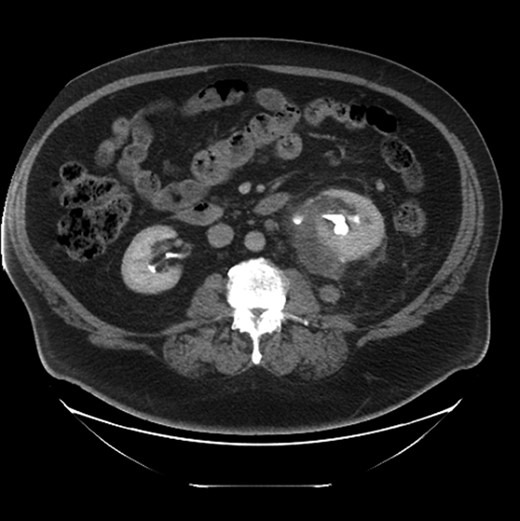

Two weeks prior to admission, he presented to a urology clinic for evaluation of micropenis and was incidentally noted to have microhematuria on urinalysis. He underwent a negative cystoscopy. He proceeded to have a computerized tomography (CT) scan that revealed a left perinephric mass with enlarged peri-renal and para-aortic lymph nodes, as well as retroperitoneal streaky changes (Fig. 1). Due to concern for malignancy, he underwent a CT-guided peri-renal lesion biopsy. Initial histopathological analysis revealed extensive areas of atypical cellular proliferation with no clear pathological diagnosis. The patient elected surveillance rather than surgical exploration.

CT scan demonstrates a fluid collection posterior and inferior to the left kidney extensive infiltrative changes extending inferiorly into the pelvis. There is a 2 cm nodule posterior to the kidney, which was biopsied, and two enlarged para-aortic nodes (not seen on this image).